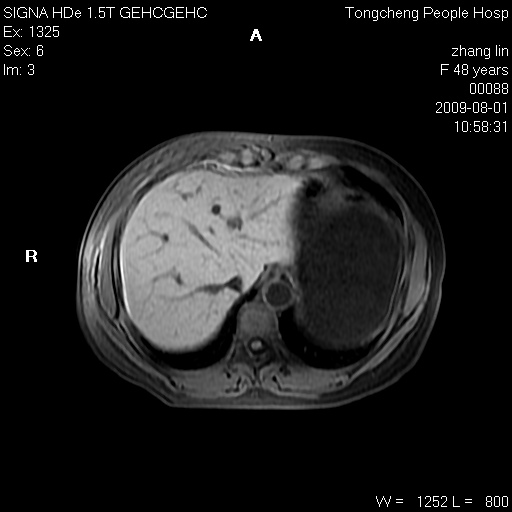

女,48岁。健康体检,彩超发现右肾占位性病变。平素健康。

临床诊断:右肾占位性病变,性质待定(囊肿?肿瘤?)。

上中腹部mr平扫+增强扫描,图像如下:

右肾上极见一类圆形病灶,t1wi呈等信号t2wi呈等高混杂信号,三期增强无强化,边界清---考虑囊肿出血。

肝囊肿

慢性胆囊炎